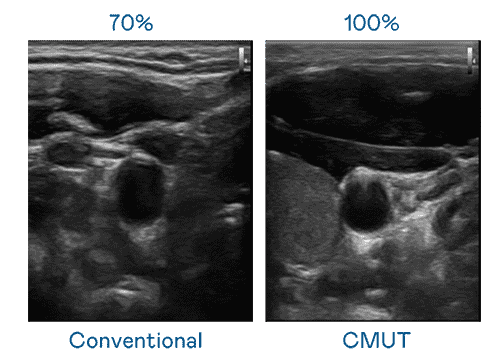

CMUT 技术是一种用电容式微机电元件来产生超音波讯号的技术。。。。与传统 PZT 压电式技术相比,,,,CMUT 频宽增加 30%,,,,更宽频的超音波讯号让影像解析度大幅提升,,,,是实现高影像品质医疗超音波扫描、、、、促进精准医疗发展的关键技术。。

大频宽带来超清晰影像

超音波影像的解析度高低,,,,首先取决于探头能发出的讯号频宽。。彩运网 CMUT 可提供高清晰的超音波讯号,,提供高频宽、、、、高灵敏度、、影像纹理细节更高的超音波影像,,,协助医护人员缩短影像判读时间及利用精准的医疗影像进行诊断。。。。